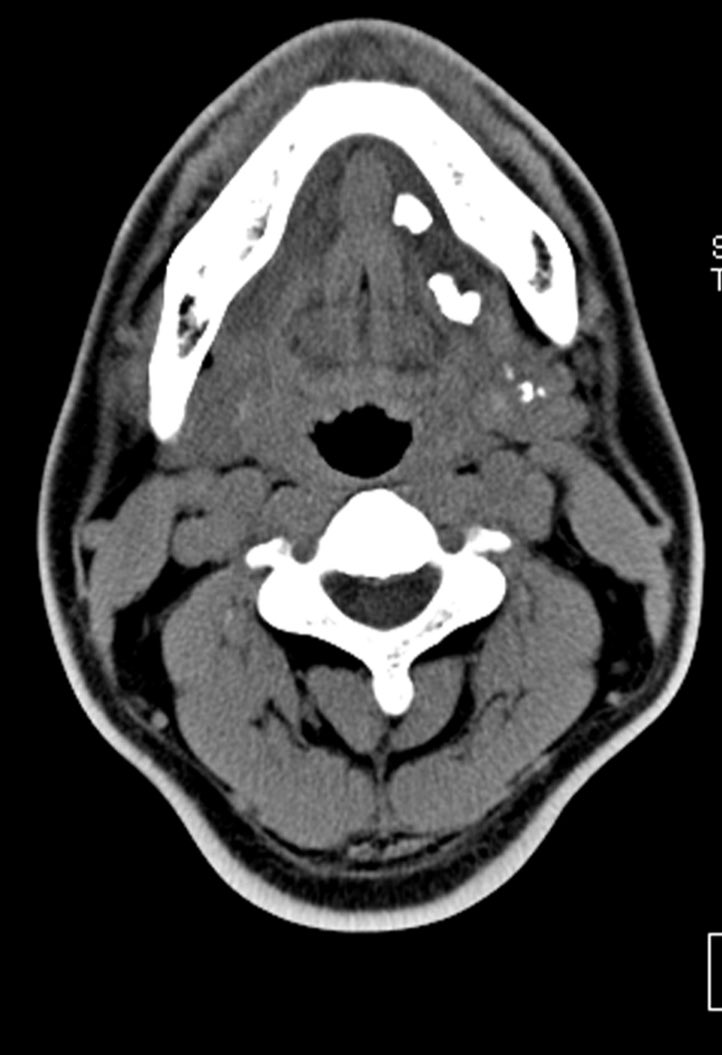

أكبرها #الغدة_النكافية والتي تقع أمام الأذن والغدة تحت الفكية بالإضافة إلى مئات الغدد الصغرى التي لاترى بالعين المجردة، وتنتشر في الفم والشفة وسقف الحلق والبلعوم. #فريد_الغامدي

الأعراض تشمل آلاما حادة عند تناول وجبات الطعام وانتفاخاً في الرقبة أو الوجه وأحيانًا حرارة وتعب، نادرا ماتتكون خراجات تحتاج إلى تدخل جراحي #عاجل

نادرًا مانحتاج إلى تدخل جراحي وذلك في حالة تكون حصيات كبيرة في قنوات الغدد أو في الغدة نفسها أو تكرر الالتهابات أو في حالة حدوث التهاب صديدي لايستجيب للمضادات الحيوية